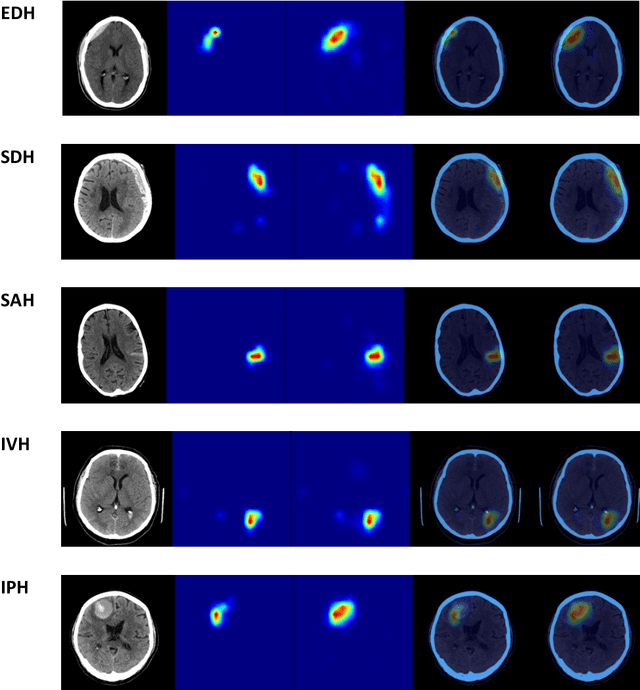

Abstract:Machine learning (ML) holds great promise in transforming healthcare. While published studies have shown the utility of ML models in interpreting medical imaging examinations, these are often evaluated under laboratory settings. The importance of real world evaluation is best illustrated by case studies that have documented successes and failures in the translation of these models into clinical environments. A key prerequisite for the clinical adoption of these technologies is demonstrating generalizable ML model performance under real world circumstances. The purpose of this study was to demonstrate that ML model generalizability is achievable in medical imaging with the detection of intracranial hemorrhage (ICH) on non-contrast computed tomography (CT) scans serving as the use case. An ML model was trained using 21,784 scans from the RSNA Intracranial Hemorrhage CT dataset while generalizability was evaluated using an external validation dataset obtained from our busy trauma and neurosurgical center. This real world external validation dataset consisted of every unenhanced head CT scan (n = 5,965) performed in our emergency department in 2019 without exclusion. The model demonstrated an AUC of 98.4%, sensitivity of 98.8%, and specificity of 98.0%, on the test dataset. On external validation, the model demonstrated an AUC of 95.4%, sensitivity of 91.3%, and specificity of 94.1%. Evaluating the ML model using a real world external validation dataset that is temporally and geographically distinct from the training dataset indicates that ML generalizability is achievable in medical imaging applications.